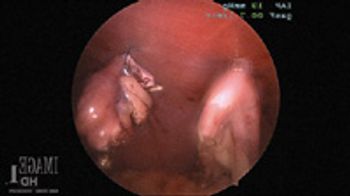

When medical management is no longer adequate, patients with tracheal collapse need more aggressive surgical intervention.